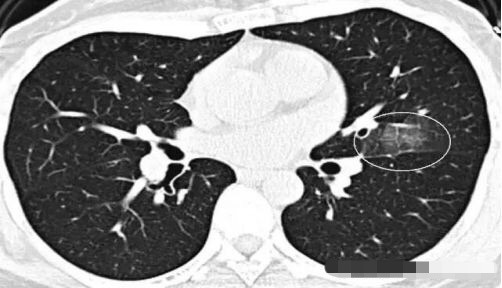

3.元芳,你看,这个也像GGO,还有一个小空洞,但它是一个隐球菌感染(肺里面长蘑菇了),不是肺癌,不用担心。